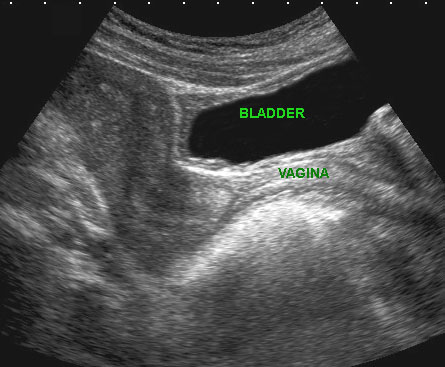

Bệnh lý của niệu đạo, âm đạo đoạn xa và cơ thắt hậu môn có thể được khảo sát bằng đầu dò âm đạo đặt ở vị trí âm hộ (mặt phẳng đứng dọc).

Hình ảnh

Giải phẫu siêu âm bình thường với đầu dò ở vị trí âm hộ